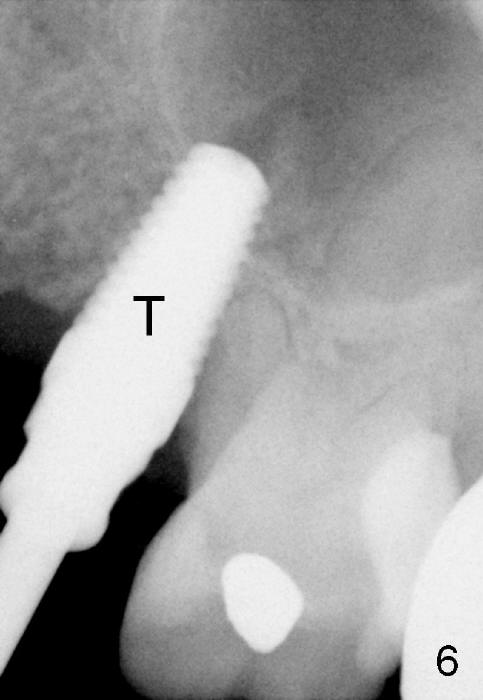

The anterior retainer is kept as a crown at #11 (Fig.2: C), whereas the residual root at the site of #13 is extracted with apical perforation (Fig.3 ^).  It is confirmed by Fig.4 (<).  To close the perforation, an osteotomy is initiated on the palatal wall of the socket with a 2 mm osteotome (Fig.5 insert: circle).  As the osteotomy is being enlarged by a 3 mm osteotome, the bone between the original socket and the osteotomy is being pushed buccally.  The former is being closed (Fig.5).  The osteotomy is finished with combination of osteotomes and reamers.  Fig.6 shows that a 5x14 mm tap is inserted at the site of #13 and that the sinus floor is lifted.  In fact the sinus membrane is partially torn at the osteotomy, which is repaired by insertion of Colla-form Dressing (Impladent), followed by autogenous bone (harvested from reamers) mixed with Osteogen  (Impladent).  A 5x14 mm implant is placed at the site of #13 with insertion torque more than 60 Ncm (Fig.7: I).  An incision is made at the site of #12 to start osteotomy with insertion of a parallel pin (Fig.7 P).  A 3 mm reamer is kept in place for position confirmation (Fig.8 R).  Due to ridge atrophy (Fig.2 arrowheads), a much smaller, but longer implant is placed at the site of #12 (Fig.9: 4x17 mm).  The autogenous bone harvested from #12 osteotomy is placed in the buccal gap of #13, followed by insertion of Colla-form Dressing (Fig.10 M).  To protect the membrane, a short abutment (4x3 mm) is temporarily placed (Fig.9,10 A) and perio dressing (Fig.9 D) is applied around the abutment and the interproximal areas of the neighboring teeth.  Usually perio dressing dislodges around 1 week postop, particularly for a large edentulous space.  In this case, the dressing is quite stable 11 days postop: the abutment (Fig.11 A) appears to contribute to retention of the dressing (D).